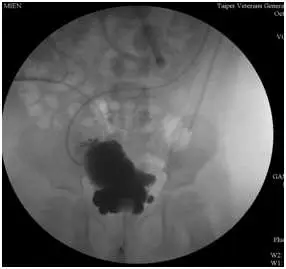

從提供的兩張 VCUG 影像可見:

- 膀胱明顯增大,壁呈肥厚及不規則的trabeculation,並見多發小型凸出形成的膀胱憩室(diverticula);

上述改變符合 PUV 導致的阻塞後壓力過高,使膀胱壁肥厚形成trabeculae及憩室,同時後段尿道於排尿期因瓣膜阻塞而擴張(obgynkey.com)。